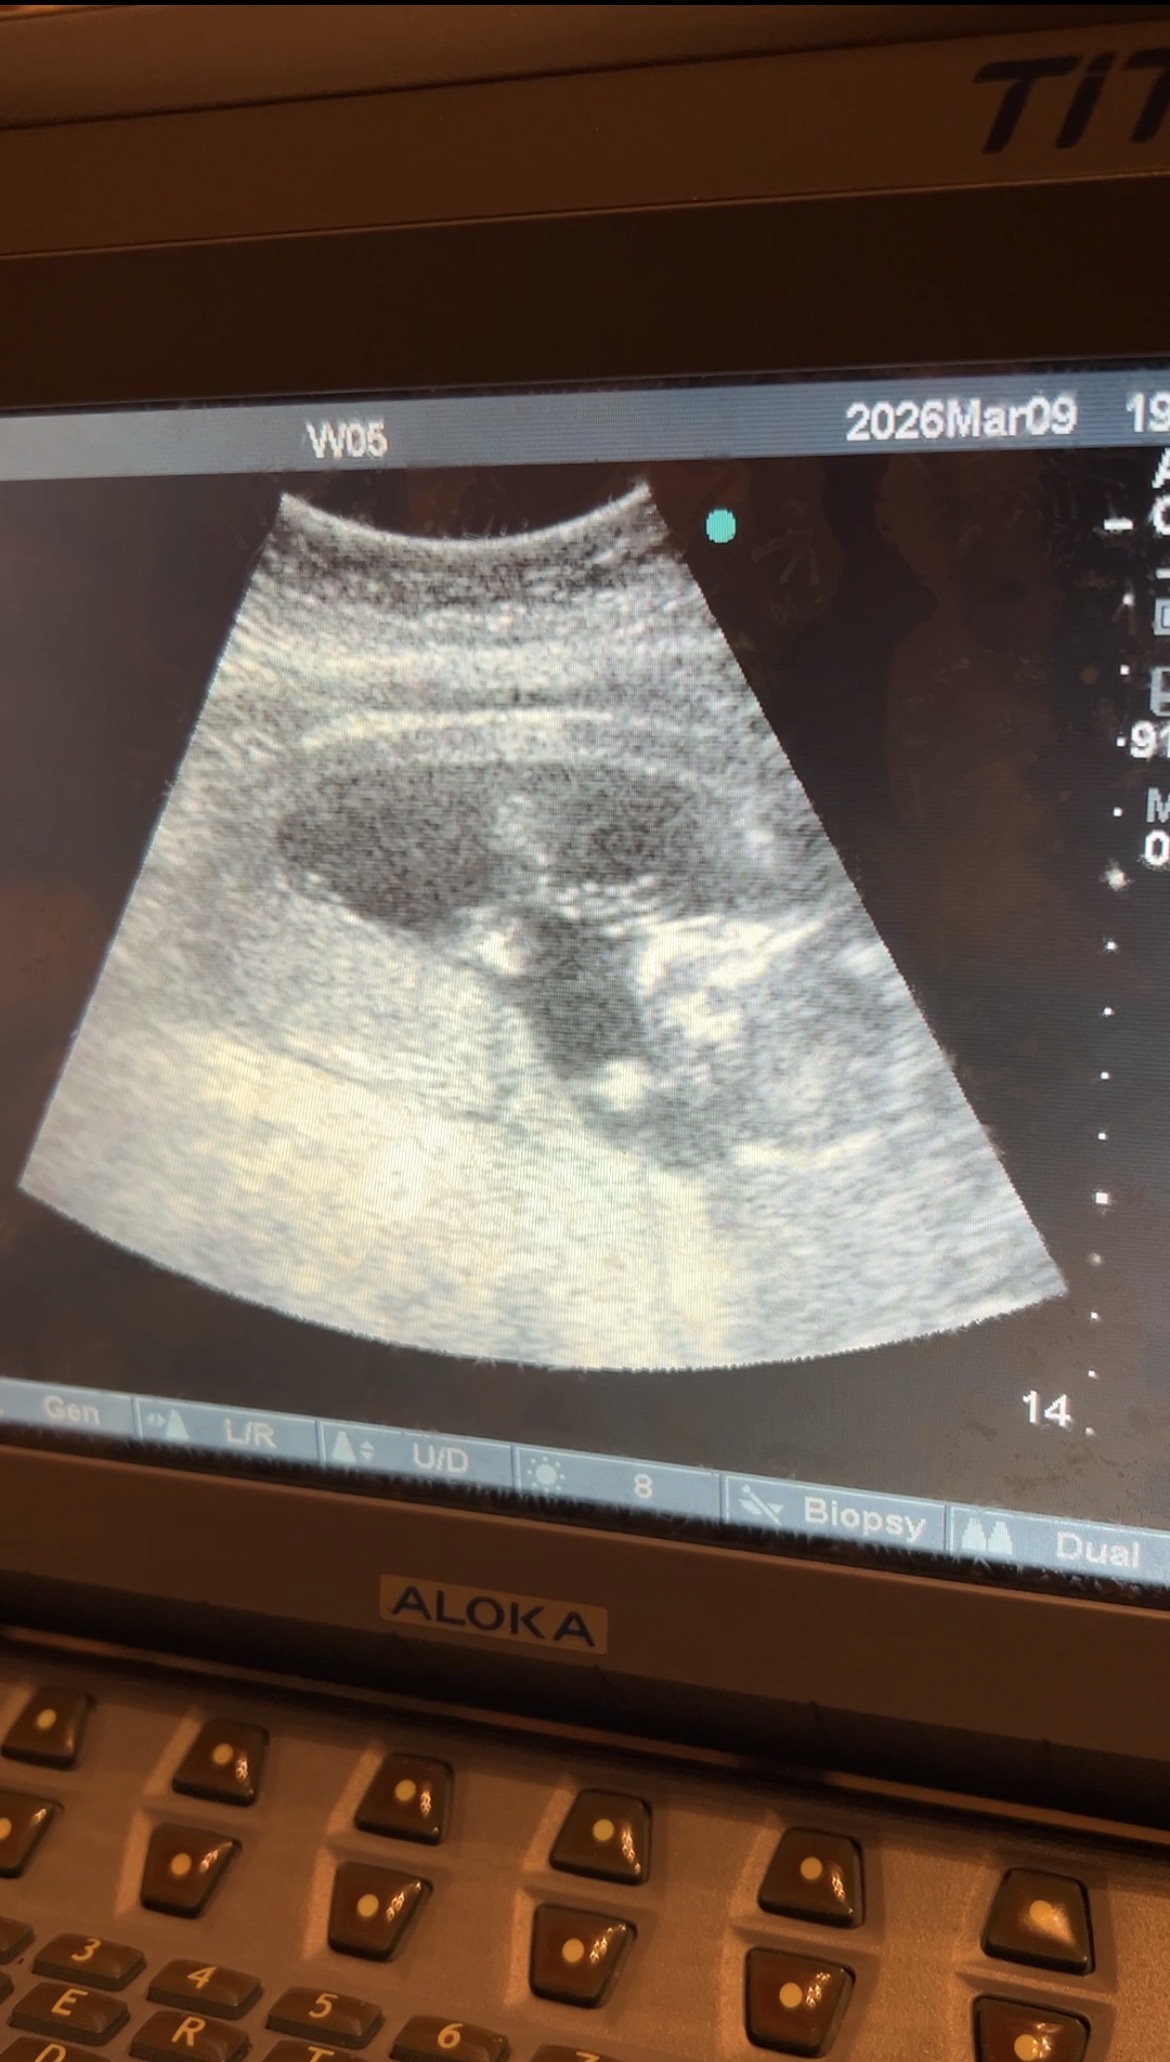

エコーで赤ちゃんの状態を確認してから

足つぼと鍼治療を行いました。

お渡ししたエコー動画を

旦那さんに見せたところ

とても喜んでくれたそうです☺️